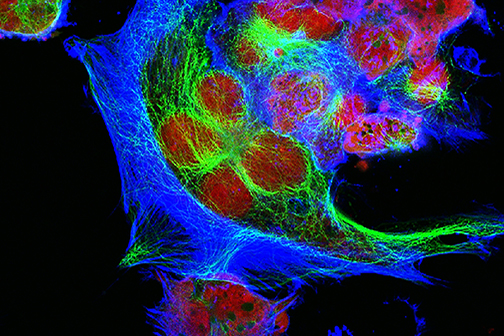

LSU Health New Orleans Develops New Human Cell Line to Study Blinding Eye Disorders

Under the direction of Boyd Professor Nicolas Bazan, MD, PhD, scientists at LSU Health New Orleans Neuroscience Center of Excellence have developed a new, experimental human cell line from retinal pigment epithelial cells. Called ABC, these cells so closely resemble and retain the properties of native retinal pigment epithelial (RPE) cells, the research team has shown that they are a reliable cell system to study retinal degenerative diseases. More